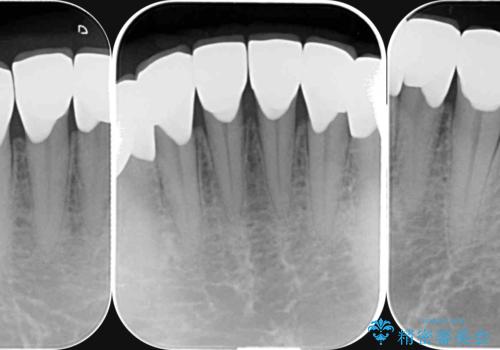

- 歯ぎしり・嘔吐症により歯がすり減ってしまい、色調・見た目を改善したいと来院されました。

神経を温存したまま仮歯に置き換え、噛み合わせの安定を確認したのちに すり減りに強いジルコニアクラウンで最終的な仕上げを行います。

歯の形態・色調を大きく変更する場合ジルコニアクラウンによる治療が耐摩耗性・審美性の観点から推奨されます。